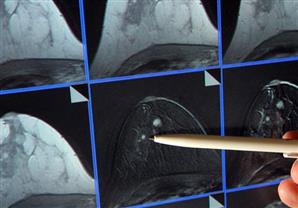

والهيكل العظمي الذي أجريت الدراسة عليه يرجع إلى عصر الأسرة السادسة (2345-2181 قبل الميلاد) ويوجد في مقبرة غربي مدينة أسوان الواقعة على بعد نحو 900 كيلومتر جنوبي القاهرة. وقال ممدوح الدماطي، وزير الآثار المصري، في البيان إنّ الدراسة التي تجريها بعثة جامعة جين الإسبانية -بالتعاون مع وزارة الآثار- على الهياكل العظمية في جبانة قبة الهواء غربي أسوان رصدت "تشوهات غير مألوفة" على الهيكل العظمي للمرأة وإن الفحص كشف عن إصابتها بسرطان الثدي.

وأضاف أن أهمية هذا الكشف في إسهامه في إضاءة "المزيد من الحقائق الأثرية والتاريخية" عن التفاصيل اليومية والظروف المعيشية في تلك الفترات البعيدة. وقال ميخيل بوتييا رئيس الفريق البحثي الانثروبولوجي إن الدراسات كشفت بقايا آثار التدهور نتيجة "انتشار ورم خبيث بين العظام" وأن المرأة كانت تنتمي إلى طبقة راقية في هذه المنطقة. وأضاف "ربما منعها مرضها من القيام بأية مهام إلا أنه من الواضح أنها حظيت بالعناية والاهتمام طوال فترة مرضها وحتى الوفاة."